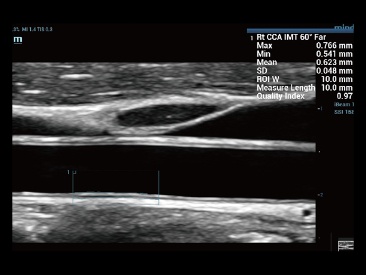

Sejak didirikan, Mindray terus mencari cara baru untuk meningkatkan keandalan diagnostik. Didukung Teknologi ZONE Sonography? terkini, platform ZST+ baru Resona 7 meningkatkan kualitas gambar ultrasound melalui pengambilan zona dan pemrosesan data saluran.

Selain kualitas gambar premium, Resona 7 juga meningkatkan kemampuan penelitian klinis dengan V Flow revolusioner untuk evaluasi hemodinamika vaskular, serta pengambilan penampang tercanggih dari rangkaian data 3D untuk diagnosis CNS pada janin. Kombinasi pengoperasian multisentuh berbasis gerakan yang paling intuitif dengan semua fitur klinis penting membuat Resona 7 menjadi gebrakan baru dalam inovasi ultrasound.